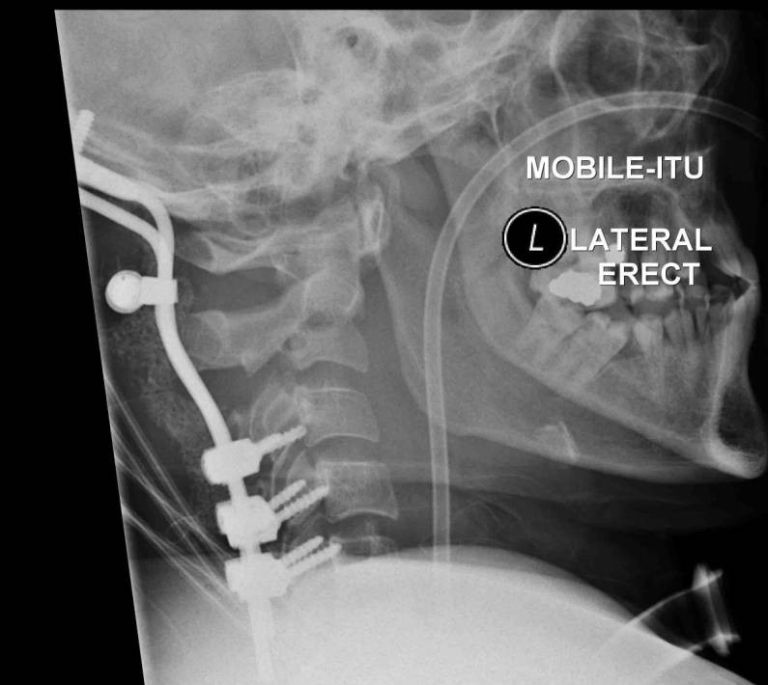

NEWCASTLE – Tony Cowan, 29 anni, è riuscito a sopravvivere, contro ogni pronostico medico, dopo che la testa è stata recisa dalla colonna vertebrale in un brutto incidente.

I tessuti muscolari hanno evitato che si staccasse dal collo dopo che la sua auto subì un brusco impatto dopo averne perso il controllo. Secondo quanto riporta Metro.co.uk, Tony, un ex muratore è riuscito a sopravvivere ma oggi è costretto a stare su una sedia a rotelle e a comunicare attraverso una macchina.

La sua compagna e la sua famiglia erano convinti che sarebbe morto, ma è riuscito a sopravvivere. Tony Cowan comunica grazie a una particolare macchina che emette segnali luminosi, non cammina e ha bisogno di aiuto per svolgere ogni minima azione quotidiana.